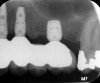

Fig 7. Tilted implant solutions for maxillary posterior partial edentulism. In the same manner that tilted implants can be used to

avoid the need for sinus grafting in full-arch implant prostheses, they can be used to avoid direct or indirect sinus grafting when insufficient posterior

maxillary bone volume challenges a fixed dental prosthesis implant restoration. Fig 7: Software planning for implant placement is shown with

tilting of the distal implant along the anterior wall of the maxillary sinus where there is insufficient bone in zone 3. Fig 8: Postoperative radiograph

of the implants and abutments reveals the angulation of the implant resolved by the CAD/CAM abutment. Fig 9: Final radiograph of the implant

prosthesis following restorations demonstrates the inclusion of a tooth in the molar position without sinus grafting.

Figure 7